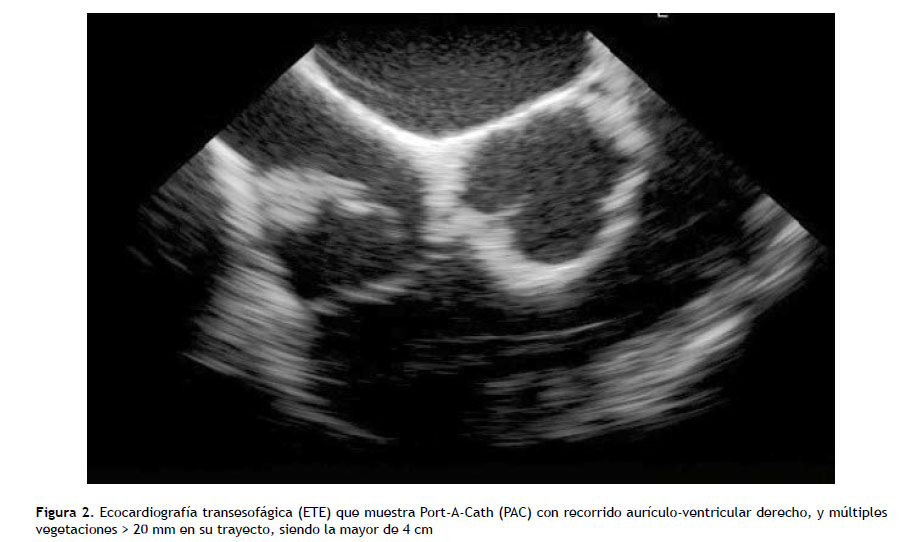

Paciente mujer de 36 años, con diagnóstico de vasculitis leucocitoclástica y uso de morfina como terapia para el dolor crónico, administrada por PAC desde hace un año, sin antecedente de episodios previos de infección del catéter. Ingresa por emergencia por 10 días de fiebre intermitente, tos y dolor torácico, con evidencia tomográfica de infiltrado pulmonar en base de hemitórax derecho y se decidió iniciar cobertura antibiótica de amplio espectro con imipenem y vancomicina. Al examen físico no se evidenció signos inflamatorios en zona externa del catéter. En el quinto día de hospitalización se reportó aislamiento de C. parapsilosis, en un set de hemocultivos periféricos tomados al ingreso, con susceptibilidad a fluconazol (CIM ≤2µg/mL), caspofungina (CIM ≤2µg/mL), anidulafungina (CIM ≤2µg/mL) y voriconazol (CIM ≤0,12µg/ mL), según antifungigrama (método automatizado Vitek2- puntos de corte aprobados CLSI/M27-S4-2012). La paciente refirió exposición previa a azoles. Inició tratamiento con caspofungina 70mg EV dosis de carga y luego 50mg EV c/24 horas por 5 días; y con hemocultivos posteriores negativos a las 48 horas más caída de la fiebre, se decide continuar tratamiento con fluconazol 800 mg/día EV hasta completar 14 días de tratamiento antifúngico. El examen de fondo de ojo fue normal, y por la aparente evolución favorable no se realizó estudio ecocardiográfico. Sin embargo, a los dos días de haber concluido la terapia antifúngica cursó con deterioro clínico evidenciándose en nueva tomografía de tórax imagen sugestiva de trombo en el extremo distal de la arteria pulmonar derecha con extensión a ramas interlobares (Figura 1), lo cual coincide con nuevo cuadro febril y dolor torácico, por lo que se realizó inmediatamente una ecocardiografía transesofágica (ETE), donde se objetivó en el PAC múltiples vegetaciones > 20 mm en su trayecto, siendo la mayor de 4 cm (Figura 2).